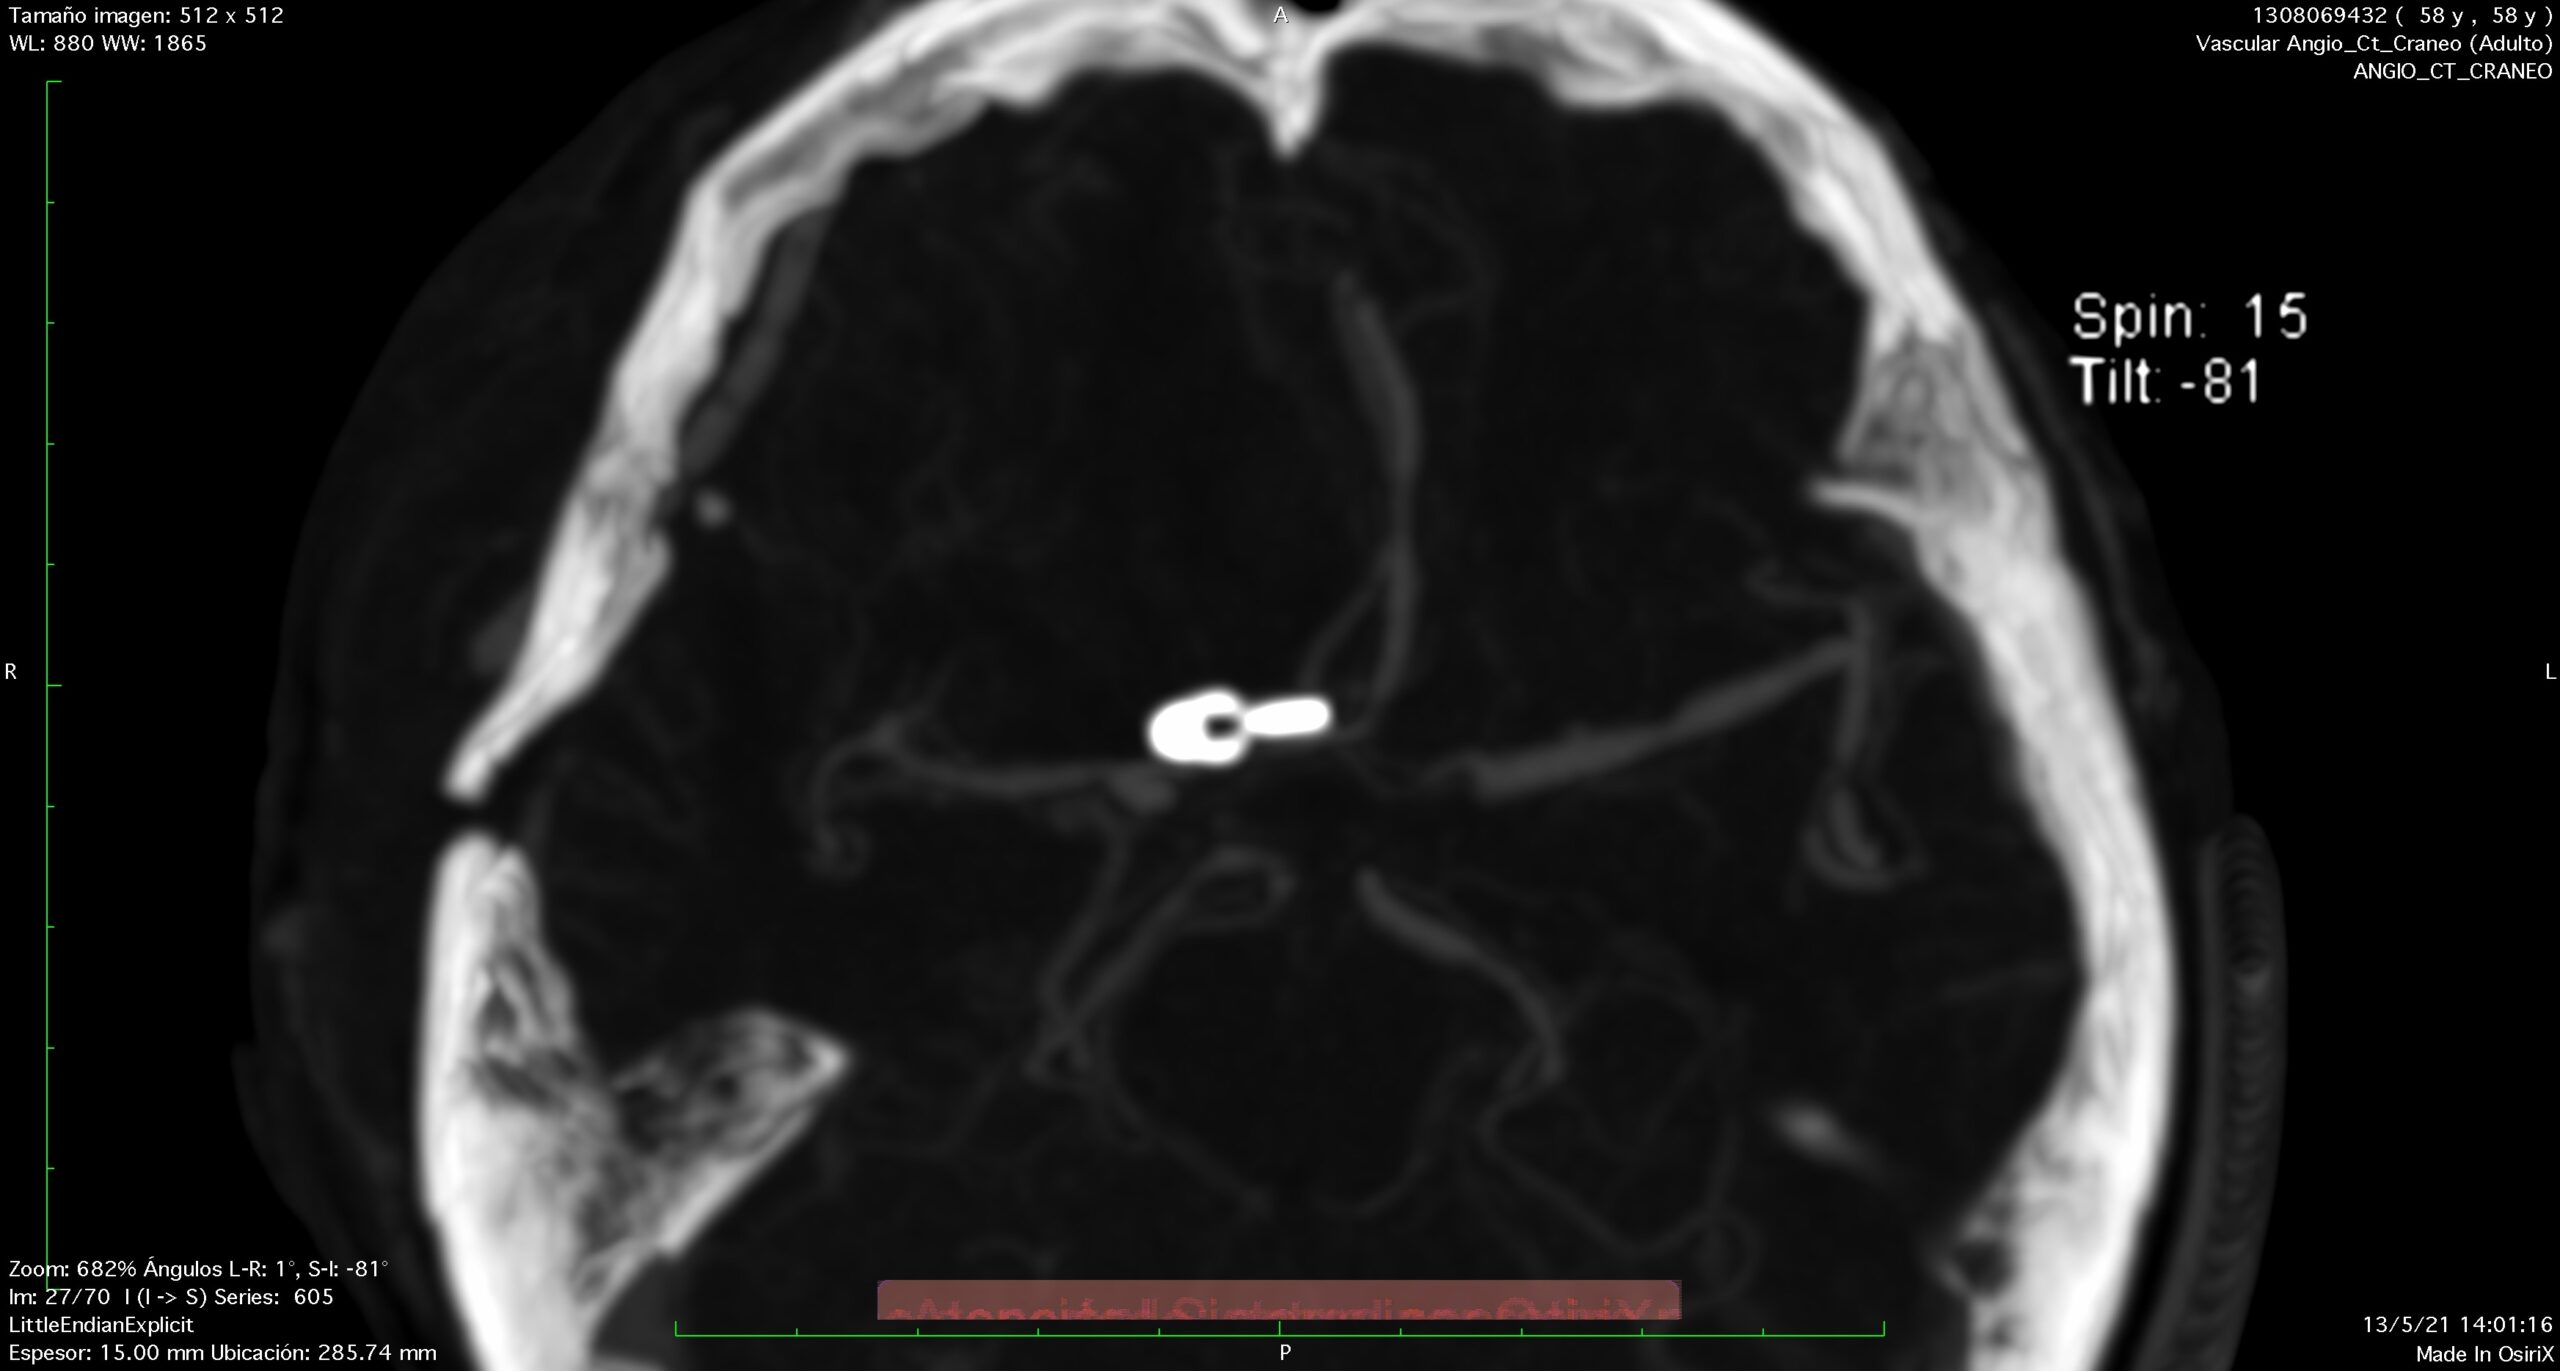

Aneurisma recurrente visto cerca de clips

Angiografía cerebral 3D que muestra un aneurisma